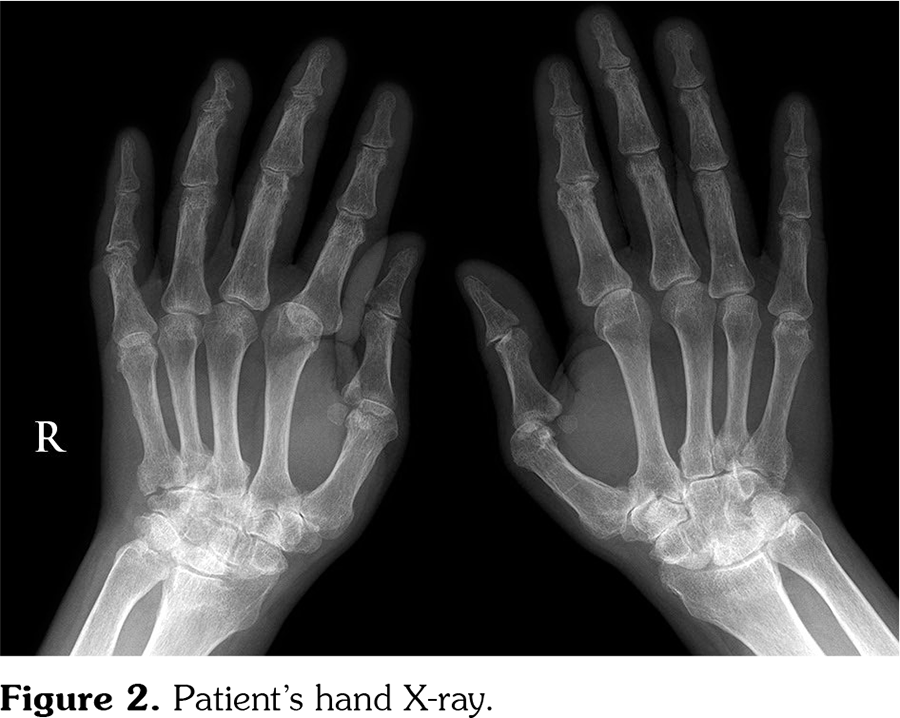

A 45-year-old male patient with RA was referred for newly onset skin rashes on his arms and legs after starting the treatment with tofacitinib (Figure 1). He was taking methotrexate 5 mg/weekly, folic acid 5 mg/weekly and tofacitinib 5 mg twice a day for RA. Disease had started nine years ago, first with pain and swallowing on his ankle. Within one year, arthritis developed on wrist, metacarpophalangeal (MCP) and proximal interphalangeal (PIP) joints, with no involvement in distal interphalangeal (DIP) joints. The patient had no inflammatory back pain symptoms. Psoriasis was not present in his or his family’s medical history. Laboratory tests were negative for antinuclear antibody, extractable nuclear antigen profile, anti-cyclic citrullinated peptide, rheumatoid factor and human leukocyte antigen B27. Erythrocyte sedimentation rate was 26 mm/hour and C-reactive protein was 12.6 mg/L (0-5 mg/L). There were bilateral ulnar styloid erosions, carpal erosions and osteopenia on his hand X-ray; marginal erosions on fifth MCP, second MCP, third PIP joint, subluxation on second MCP joint on right hand; joint erosion and subluxation of first MCP, erosion and joint space narrowing of second PIP joint on left hand (Figure 2). DIP joints were normal on both hands except two osteophytes. On his pelvis anteroposterior X-ray, sacroiliac joint spaces were normal (Figure 3). Patient’s type of joint involvement and radiological findings were consistent with RA but not psoriatic arthritis. In this course, he had used methotrexate, sulfasalazine, leflunomide, hydroxychloroquine and glucocorticoids at different times. Because of the ineffectiveness of the conventional synthetic disease-modifying anti-rheumatic drugs, etanercept was started. Then, etanercept induced skin rashes with unknown characteristics and was stopped subsequently. After improving of the skin rashes, rituximab was started but discontinued due to the ineffectiveness. Tofacitinib was started when his disease activity was high (disease activity score-28 [DAS28] >5.1). Skin rashes appeared on the third month of the tofacitinib therapy while disease activity was low (DAS28=2.8). We consulted the dermatology. Dermatological examination revealed multiple, clearly demarcated, silvery, squamous and erythematous papules and plaques on the arms, legs, and ankles. Skin biopsy was performed. Epidermal parakeratosis, hyperkeratosis, focal hypogranulosis, and acanthosis with elongation of the rete ridges were observed in the skin biopsy. He was diagnosed with psoriasis. We decided that tofacitinib induced psoriasiform lesions, so tofacitinib was discontinued and leflunomide was started. After two months, lesions were improved. A written informed consent was obtained from the patient.